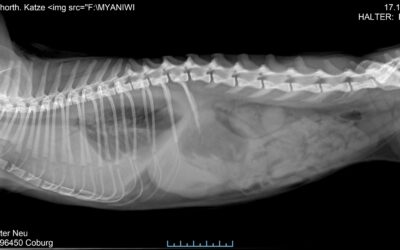

Alte Katze oder kranke Katze

Heute möchte ich…